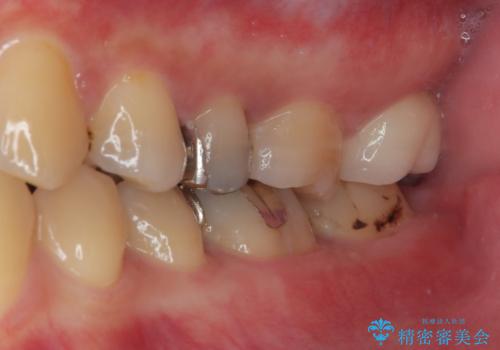

拡大鏡視野下でコンポジットレジン、虫歯を除去しオールセラミッククラウンに適した形に整えました。

歯と歯茎の間に圧排糸と言われる糸を入れてシリコーン印象材にて型どりをしました。

見た目、機能面共に満足していただけました。

今後もメンテナンスで通ってもらいながら、治療が必要になってきたところは順次行っていく予定です。